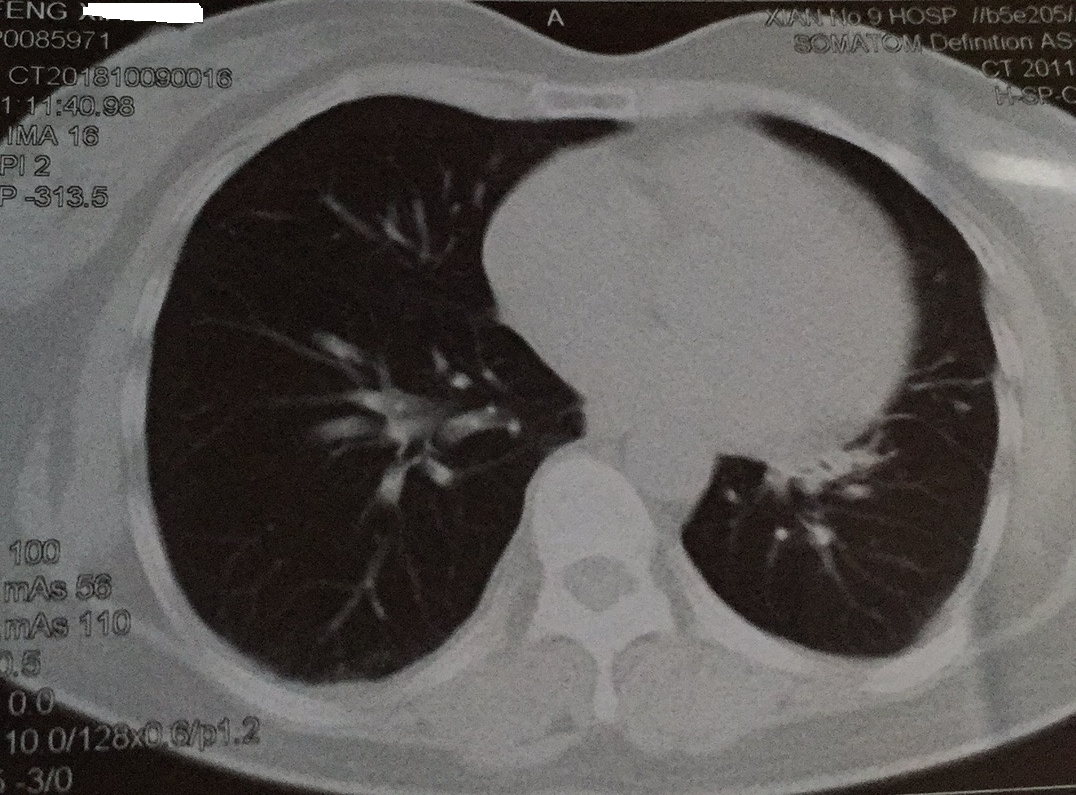

双肺弥漫粟粒性结节影